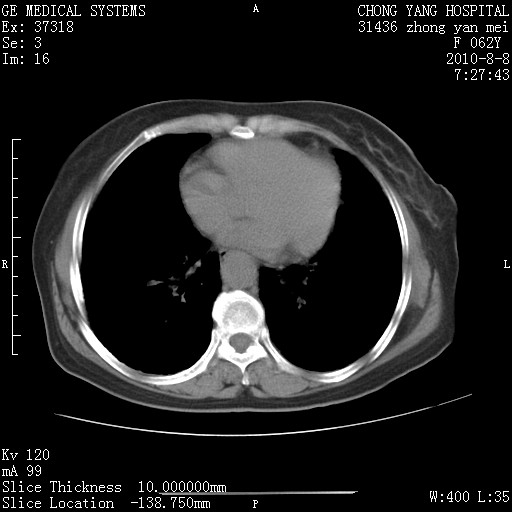

另见右乳腺似有小钙化灶,建议进一步检查。

1.肺间质纤维化.

2.纵隔淋巴结肿大。

3.迷走右锁骨下动脉。